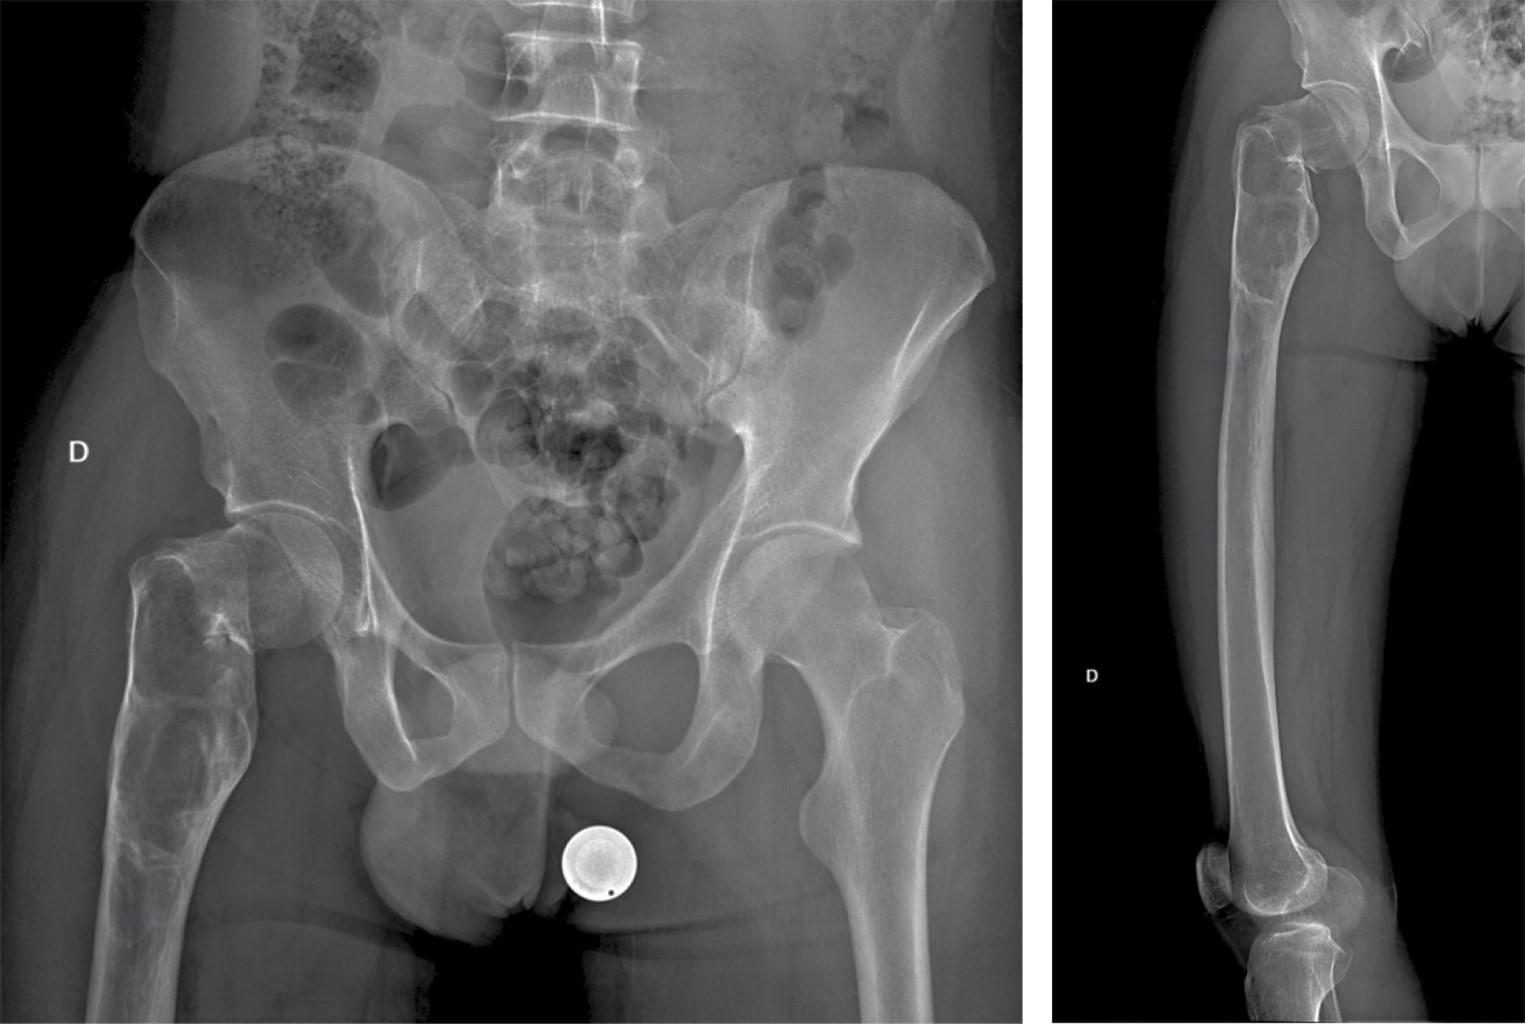

Se realizaron radiografías de pelvis y de fémur, que revelaron una fractura basicervical de fémur derecho Garden II Pauwells III AO 31B2.3r, con un patrón lítico de destrucción geográfica y un margen esclerótico bien delimitado que se extendía hacia el fémur distal aproximadamente 14 cm, sin evidencia de reacción endóstica o perióstica (Figura 1). Estas imágenes eran compatibles con una lesión de lento crecimiento, que necesitaba confirmación mediante histopatología, ya que, como se mencionó previamente, a pesar de que el paciente cuenta con antecedente de DF, existen otras entidades, algunas de comportamiento biológico maligno, de las cuales debe hacerse diagnóstico diferencial. Como estudio complementario, se realizó una tomografía simple de fémur derecho, ya que nos permite delimitar perfectamente los bordes de la tumoración para la planeación quirúrgica, así como precisar el patrón de destrucción lítico y el adelgazamiento del hueso cortical (Figura 2). Los parámetros del metabolismo óseo se encontraban dentro de valores normales.

Figura 1